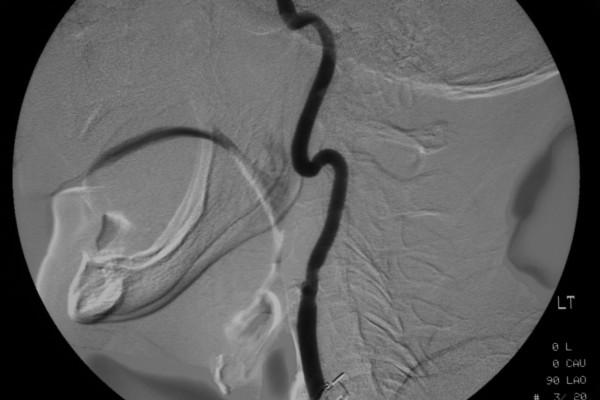

Sphenopalatine-sphenopalatine anastomosis: a unique cause of intractable epistaxis, safely treated with microcatheter embolization: a case report.

Epistaxis is the most common emergency presenting to the ENT surgeon. Here we present a case of epistaxis arising from the sphenopalatine artery in a patient who had previously had the ipsilateral external carotid artery ligated due to previous epistaxis. On investigation the epistaxis was determined to arise from an anastamosis with the contralateral sphenopalatine artery. The anatomy was demonstrated with angiography and the epistaxis treated using microcatheter embolization. Anatomical variation can be a cause for failure of ligation as a permanent treatment for epistaxis. Embolization is used less frequently for epistaxis control due to concerns about the risks involved, but it can be a valuable treatment option in intractable epistaxis following a failure of arterial ligation.